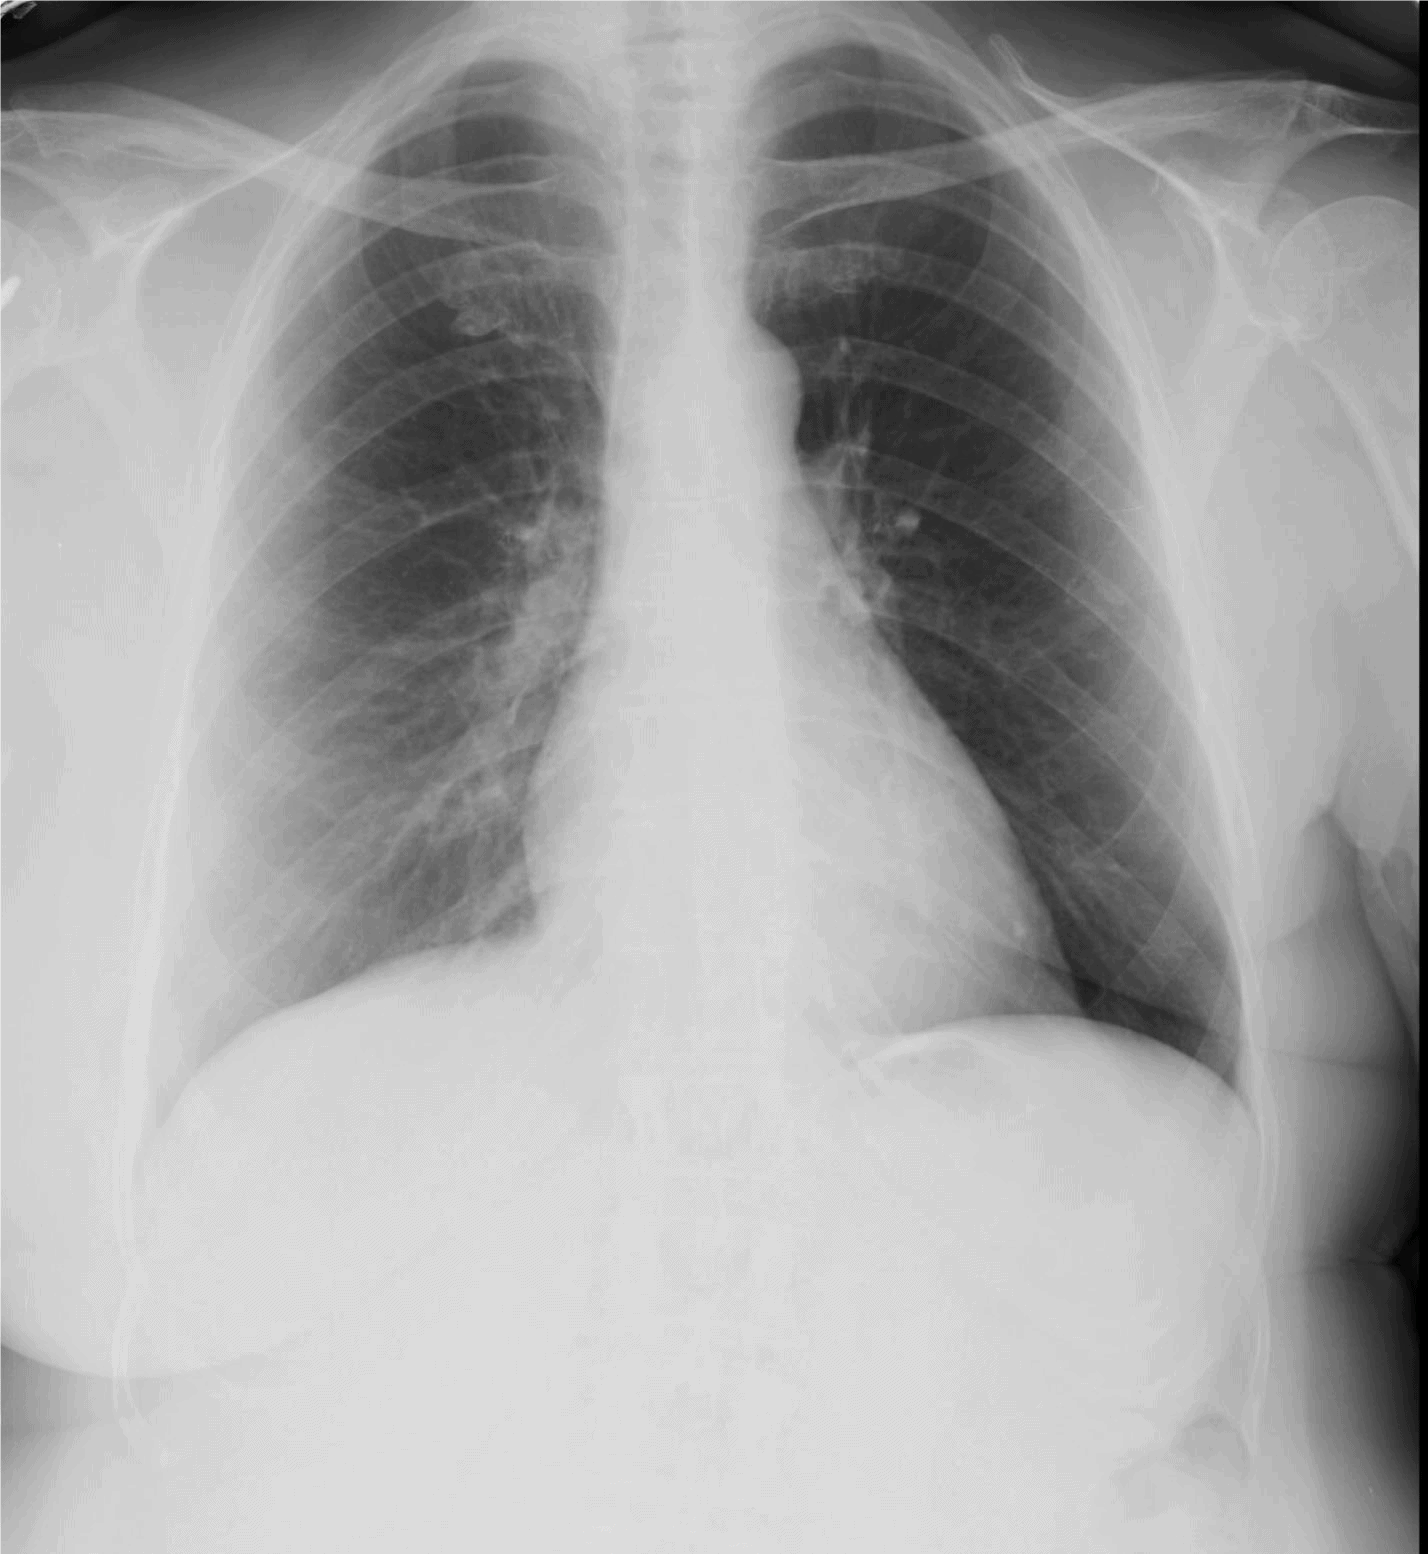

The patient is a 63-year-old woman who presents to the urgent care center with 4 days of dry cough. PMH: Breast cancer distant past. PSH: Mastectomy

View the image taken and consider what the diagnosis or next steps might be.

A 63-Year-Old Woman with a 4-Day History of Coughing